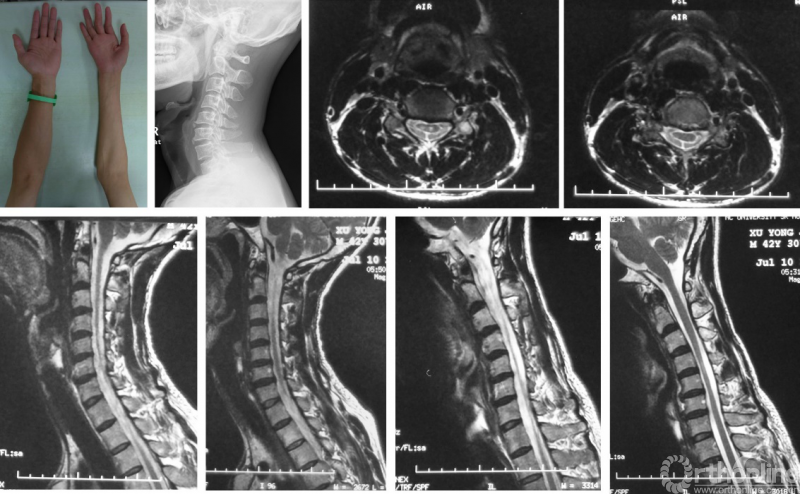

病例五:男,42岁,主诉:右上肢无力、肌肉萎缩20余年,近期左上肢出现萎缩。

体检:右上臂、前臂肌及右手内在肌萎缩,肌力III-IV级;左手内在肌萎缩、握力IV级;双膝反射(++++),右侧Hoffmann征(+),左侧Hoffmann征(-);双侧Babinski征(-)。